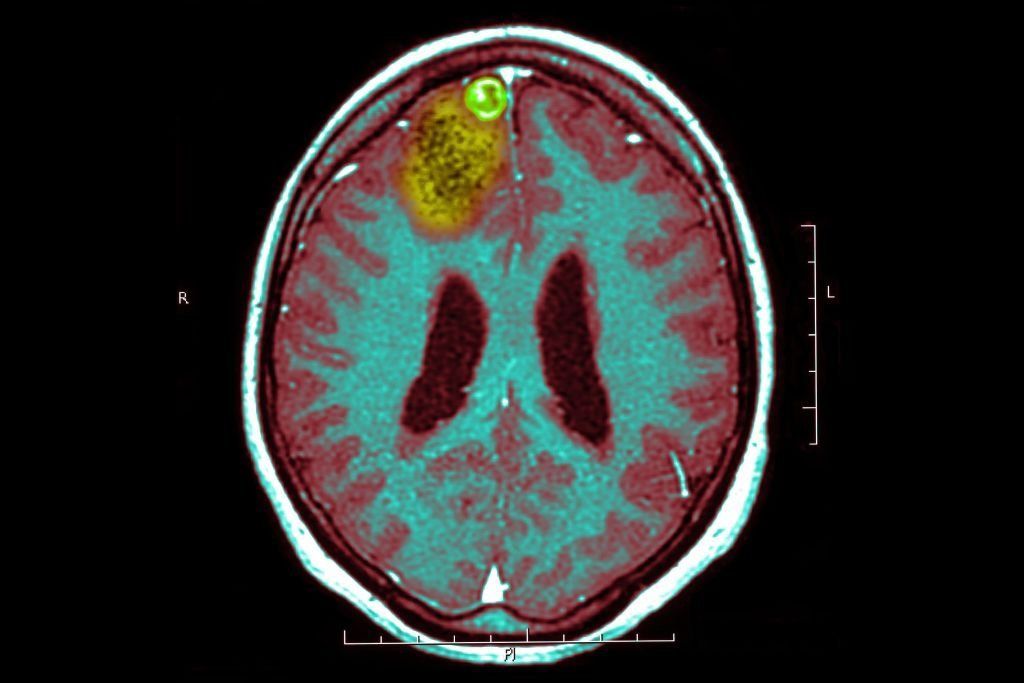

Former President Joe Biden announced to the world this past Sunday that he was diagnosed with stage four prostate cancer — which has unfortunately already metastasized and spread to his bones.

The Gleason score measures the severity of Biden’s prostate cancer at a 9/10.